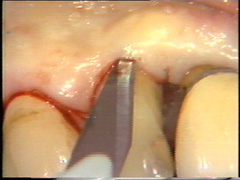

La intención de este corte es separar los tejidos adyascentes del diente (sanos) del tejido periodontal infectado (tejido de granulación, cemento infectado y cálculo) |

En palatino debe usarse el mismo principio pero la diferencia radica que el tejido palatino es muy fibroso por lo tanto el corte puede realizarse más apical para eliminar la bolsa y poder adaptar mejor el colgajo, que por ser más fibroso es menos flexible que los colgajos bucales. |